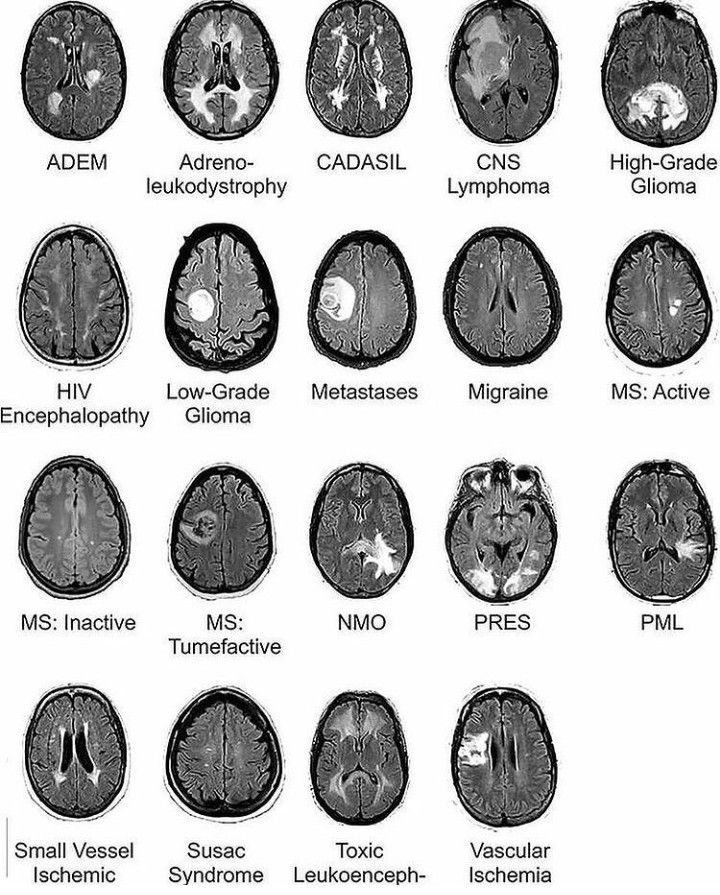

MRI of brain in different diseases

Although it's not always so textbook, it's a nice reference starting point!